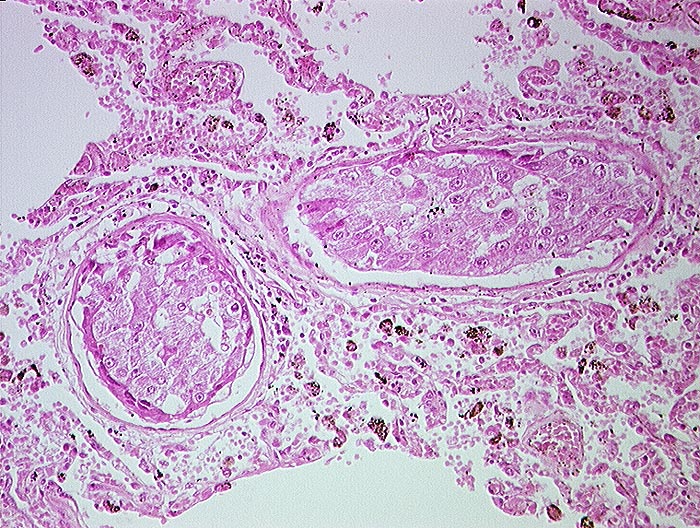

PathoPic ID 1279 - Hepatozelluläres Karzinom : Tumorembolien

Hepatozelluläres Karzinom : Tumorembolien

maligner Tumor

Lunge

Solide

Tumorzellaggregate in Pulmonalarterienästen. Die Tumorzellen haben grosse Ähnlichkeit mit Leberzellen.

Hepatozelluläre Karzinome haben die Tendenz sich in Form von Tumorembolien in die Lungen auszubreiten.

Histologie